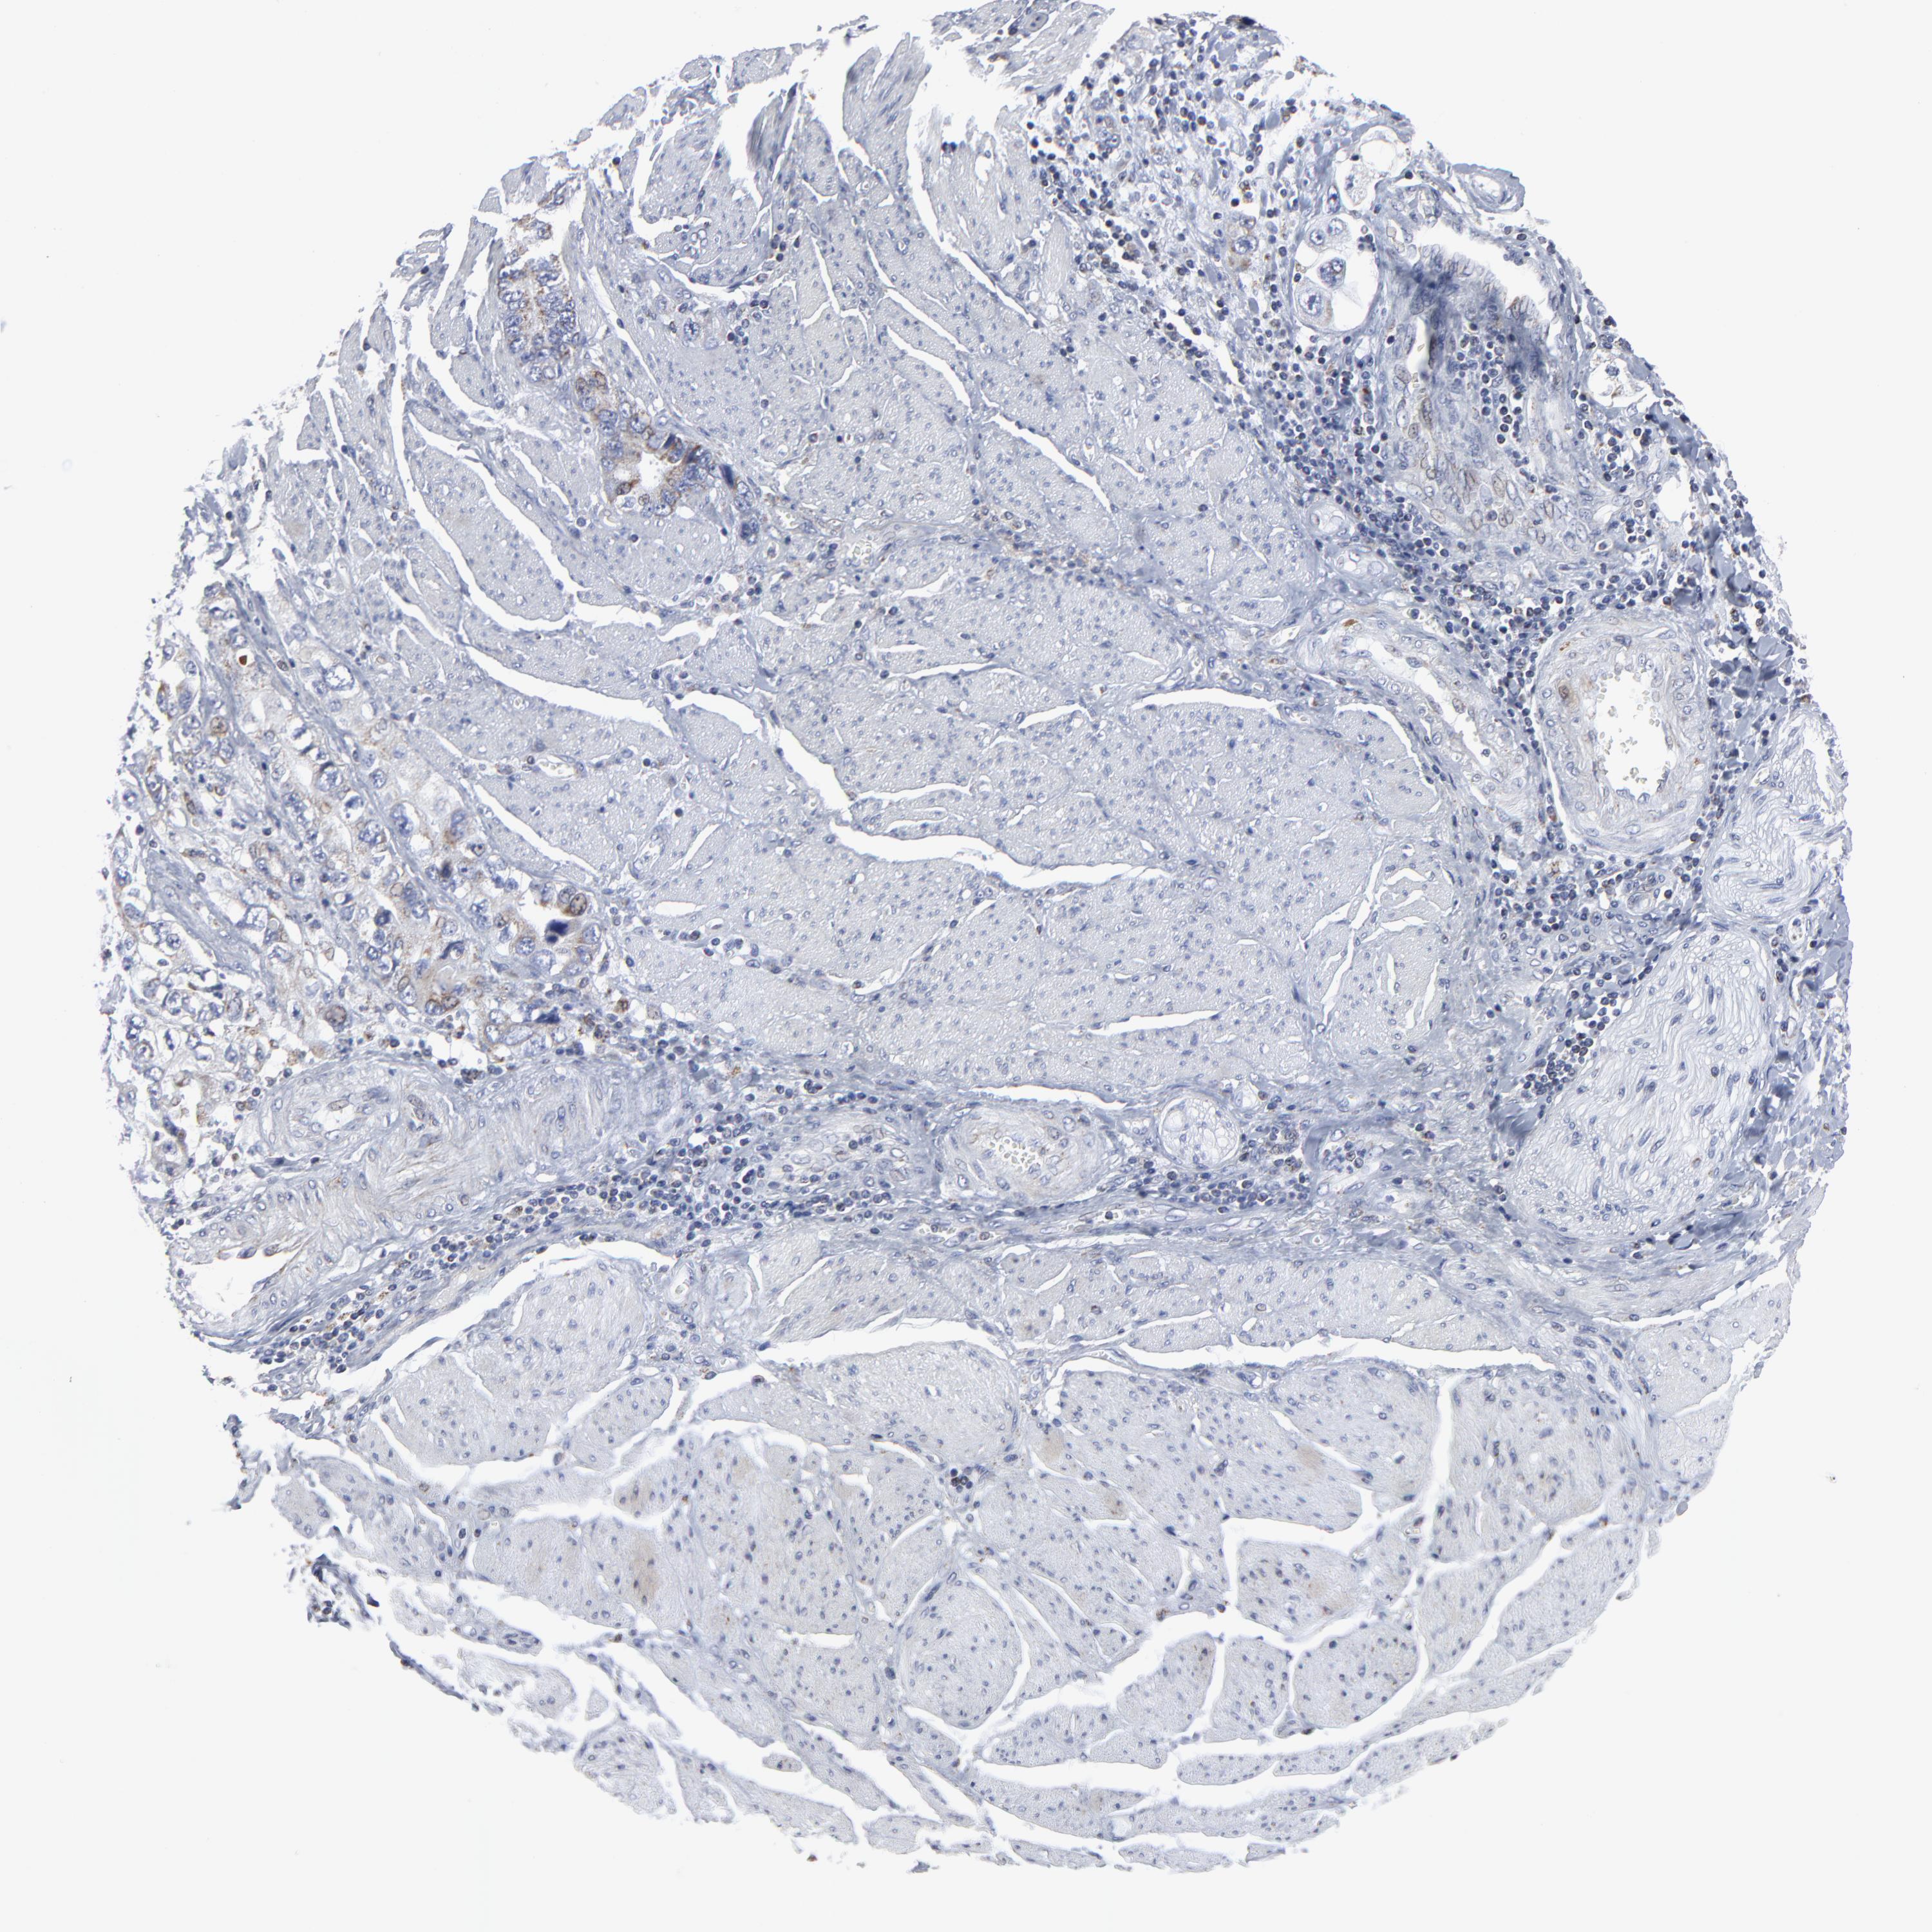

STOMACH CANCER - Protein expressioni

A mouse-over function shows sample information and annotation data. Click on an image to view it in a full screen mode. Samples can be filtered based on level of antibody staining by selecting one or several of the following categories: high, medium, low and not detected. The assay and annotation is described here.

Note that samples used for immunohistochemistry by the Human Protein Atlas do not correspond to samples in the TCGA dataset.

Antibody stainingi

Antibody staining in the annotated cell types in the current human tissue is reported as not detected, low, medium, or high, based on conventional immunohistochemistry profiling in selected tissues. This score is based on the combination of the staining intensity and fraction of stained cells.

Each image is clickable and will lead to virtual microscopy that enables deeper exploration of all samples and also displays staining intensity scores, fraction scores and subcellular localization as well as patient and tissue information for each sample.

Antibody HPA003323

Antibody CAB002007

Staining

High

Medium

Low

Not detected

Intensity

Strong

Moderate

Weak

Negative

Quantity

>75%

75%-25%

<25%

None

Location

Nuclear

Cytoplasmic/membranous

Cytoplasmic/membranous,nuclear

Adenocarcinoma, NOS